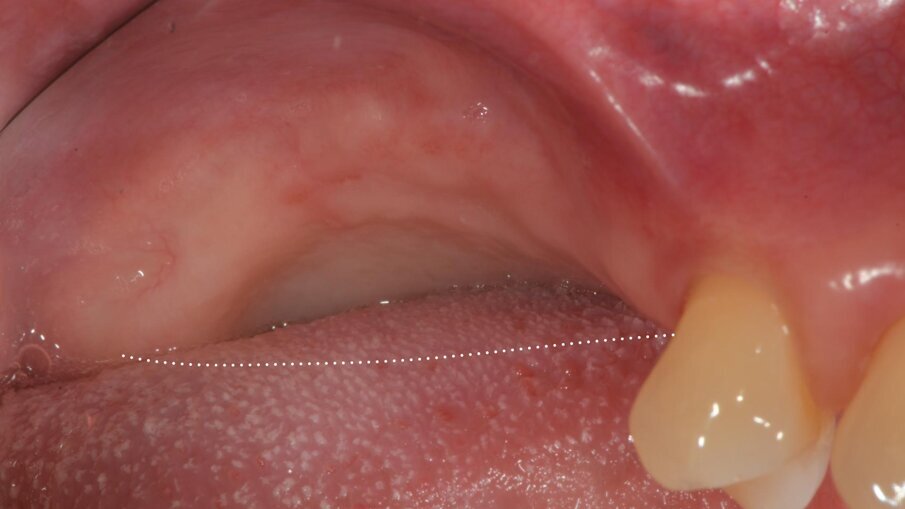

Una paziente di 62 anni, ASA I, non fumatrice e non diabetica, con malattia parodontale precedentemente trattata, si è presentata per una riabilitazione implanto-protesica del mascellare superiore (Fig. 1). L’analisi radiografica, eseguita tramite ortopantomografia (OPT) e tomografia computerizzata cone-beam (CBCT), ha rilevato la presenza di un difetto osseo verticale nel primo sestante, dovuto alla completa perdita del processo alveolare (Figg. 2, 3). Dopo aver discusso con la paziente le possibilità di trattamento, è stato accettato il trattamento proposto come prima scelta, ovvero la ricostruzione ossea del processo alveolare e la successiva riabilitazione mediante corone singole su impianti.

Il piano di trattamento è stato sviluppato utilizzando un flusso di lavoro completamente digitale. Pertanto, i files .DICOM ottenuti dalla CBCT pre-operatoria sono stati utilizzati per generare una ricostruzione 3D del mascellare, che ha permesso di eseguire la progettazione virtuale del volume osseo “ideale” per l’inserimento di 3 impianti in sede #15, #16, e #17. (Figg. 4, 5). Successivamente, è stata creata virtualmente la griglia customizzata corrispondente al volume aumentato nel mascellare della paziente (Fig. 6). Il giorno della chirurgia ricostruttiva (T0), è stata eseguita una profilassi antibiotica (2 g di amoxicillina con acido clavulanico e 500 mg di metronidazolo), una profilassi antinfiammatoria (20 mg di piroxicam), una sedazione cosciente x os (2 ml di delorazepam e 2 ml di diazepam), e disinfezione del cavo orale (risciacquo orale con povidone-iodio per un minuto, perossido di idrogeno per due minuti, e collutorio alla clorexidina 0,2% per tre minuti), e un’anestesia locale mediante articaina 4% contenente adrenalina 1:100.00018. L’esame obiettivo mostra la gravità del difetto osseo che determina un evidente difetto di volume sia in senso orizzontale che in senso verticale (Figg. 7, 8).